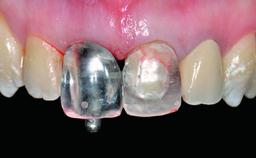

A 32-year-old female Caucasian patient with a compromised maxillary right central incisor was referred to us by a general dentist. Her chief complaints were discomfort and mobility of tooth 11 with unsatisfactory esthetics due to discoloration. The patient reported a previous trauma, some years earlier, as the origin of pathology on the afflicted tooth. Anamnesis was negative for any other dental or periodontal pathology in the remaining dentition. The patient did not take any medication and reported to be a light smoker (5–10 cigs/day). She had high esthetic expectations of her treatment. The extraoral examination revealed a high smile line with full exposure of her maxillary teeth and surrounding soft tissue in the area between the second premolars.

Lip Line No exposure of papillae Exposure of papillae Full exposure of mucosa margin

Periodontal Phenotype Low-scalloped, thick Medium-scalloped, medium-thick High-scalloped, thin

Shape of Tooth Crowns Rectangular Triangular